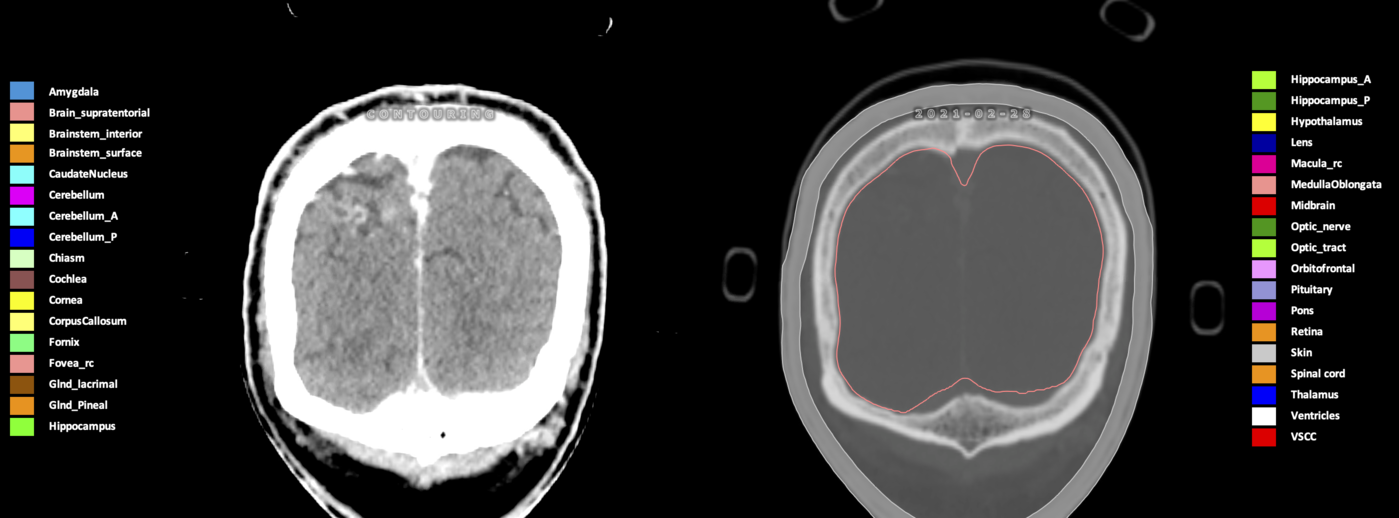

Included are all OARs known to be relevant for radiation-induced toxicity in neuro-oncology: brain, brainstem (midbrain, pons, medulla oblongata), chiasm, cerebellum (anterior & posterior), cochlea, cornea, hippocampus (anterior & posterior), hypothalamus, lens, lacrimal gland, optic nerve, pituitary, skin, and vestibular & semicircular canals. To further facilitate research on cognition, vision and radiological changes after irradiation of the brain, potential clinically-relevant OARs are included: amygdala, caudate nucleus, cerebellum (anterior & posterior), corpus callosum, fornix, macula, optic tract, orbitofrontal cortex, periventricular space (PVS), pineal gland, and thalamus.

Three-dimensional delineation of the 25 consensus OARs for neuro-oncology are shown on CT (WW/WL 120/40, 3000/600), 3T MR images, (T1Gd, T2FLAIR 1mm) and 7T MR (MP2RAGE 0.7 mm). All are presented in transversal, sagittal and coronal view.